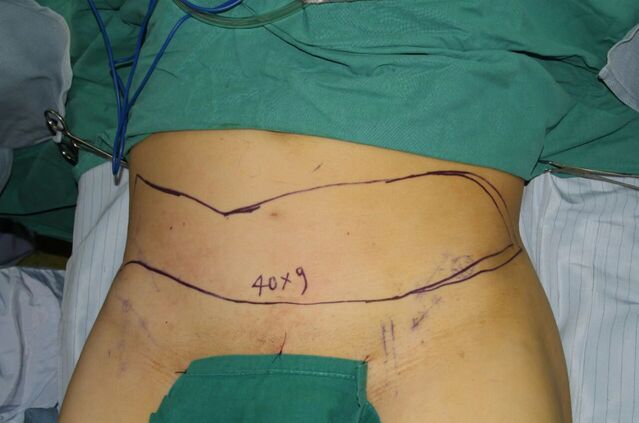

腹部横行皮瓣修复下肢长段缺损

微信图片_20230909224140.jpg 微信图片_20230909224150.jpg 微信图片_20230909224147.jpg 微信图片_20230909224204.jpg 微信图片_20230909224200.jpg 微信图片_20230909224207.jpg